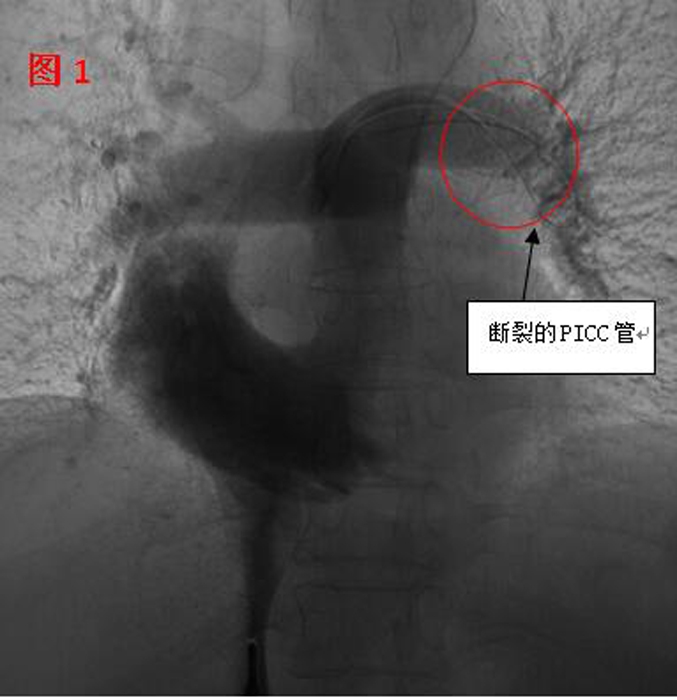

??? 11月2日,在醫(yī)院多個(gè)科室的配合下,這臺(tái)心臟異物取出術(shù)開始了。血管外科醫(yī)生在手術(shù)時(shí)發(fā)現(xiàn),斷裂的PICC管竟完全移位至病人的心室、肺動(dòng)脈(見(jiàn)圖1),情況十分棘手。術(shù)中應(yīng)用異物捕捉系統(tǒng)時(shí),由于導(dǎo)管隨心臟跳動(dòng)和呼吸的影響,擺動(dòng)巨大,捕捉后導(dǎo)管反復(fù)滑脫,且術(shù)中患者心臟稍受刺激就會(huì)出現(xiàn)心律失常。